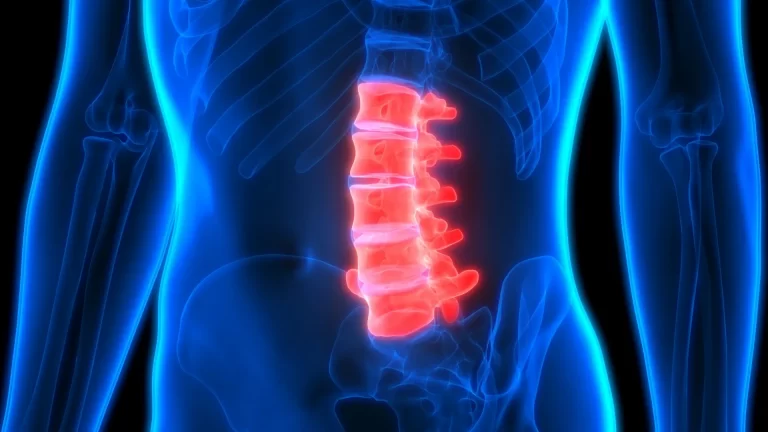

ستون فقرات، بهعنوان محور اصلی حرکت و پشتیبانی بدن، تحت تاثیر عوامل مختلفی، ممکن است دچار فرسایش و التهاب شود. آرتروز ستون فقرات، که به آن اسپوندیلوز نیز گفته میشود، یک بیماری دژنراتیو است که با تحلیل رفتن غضروف مفاصل و دیسکهای بین مهرهای همراه است. این فرایند میتواند...

سندروم دم اسبی یا سندرم کودا اکوینا، یک اختلال عصبی نادر است که به دلیل فشار شدید یا فشردگی ریشههای عصبی در انتهای نخاع، که به آن دم اسبی (cauda equina) گفته میشود، به وجود میآید. این بیماری میتواند عوارض جدی و دائمی، از جمله فلج، بیاختیاری ادرار و...

فتق یا بیرون زدگی دیسک یکی از مشکلات شایع ستون فقرات است که به دلیل فشار یا پارگی در دیسکهای بین مهرهای ایجاد میشود و باعث درد، بیحسی و ضعف در اندامها میشود. معمولا افرادی که بیشتر از ۳۰ سال دارند دچار این بیماری میشوند، اما سن تنها عامل...